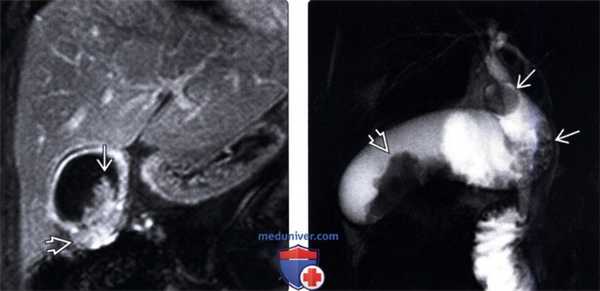

(Левый) При динамической МРТ в постгадолиниевую фазу в корональной плоскости наблюдается отсроченное прогрессирующее накопление контраста дольчатым полипоидным образованием, также виден дефект контрастной стенки желчного пузыря.

(Правый) У этого же пациента при МР холангиопанкреатографии определяются конкременты шейки и тела желчного пузыря и дольчатое полипоидное образование, пролабирующее в просвет желчного пузыря.